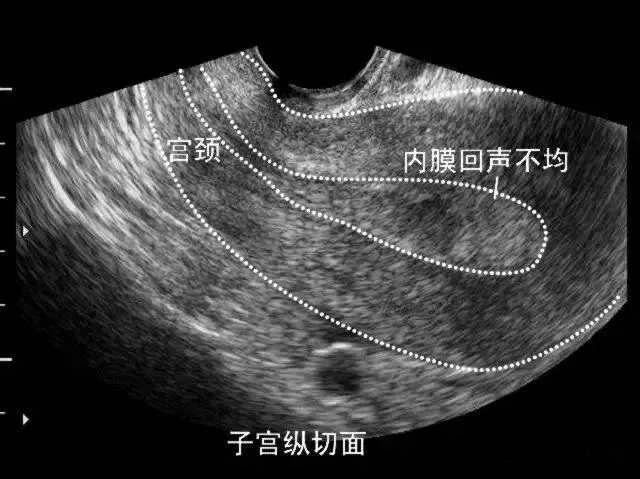

●声像图表现:宫腔内线性、圆形或三角形强回声。

●宫内节育器位置正常:节育器强回声位于宫腔中心,其周围内膜显示为低回声的晕圈。在子宫纵切面可判断宫内节育器在宫腔内的位置正常位置的宫内节育器应全部位于宫腔内,且节育器最下缘不低于宫颈内口。

宫内节育器位置异常声像图